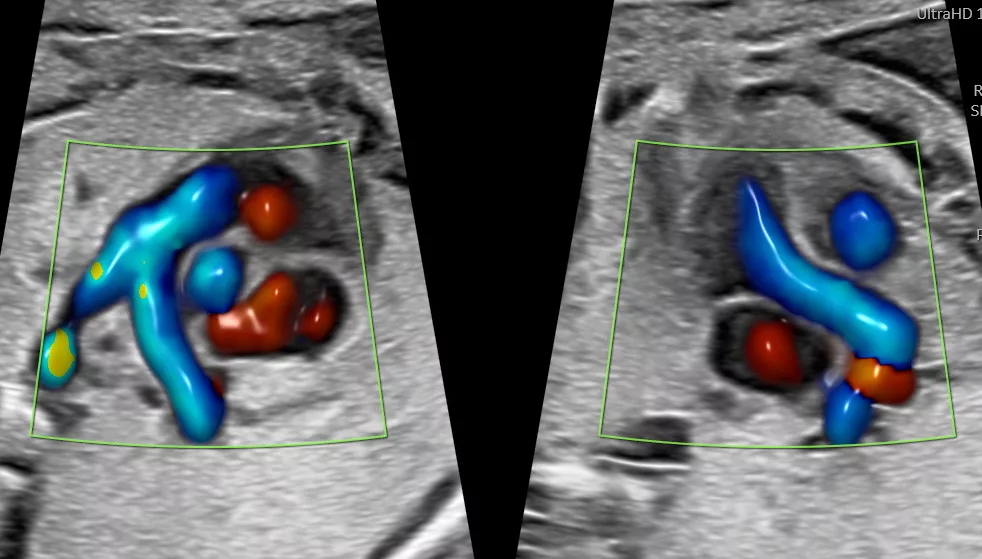

Mme Alexandrine AUFFRET-FAURE est une sage-femme échographiste. Elle pratique des échographies de dépistage aux trois trimestres de la grossesse et effectue des actes d’échographies pelviennes et gynécologiques.

Pratique de l’échographie obstétricale exclusive

Depuis 2017